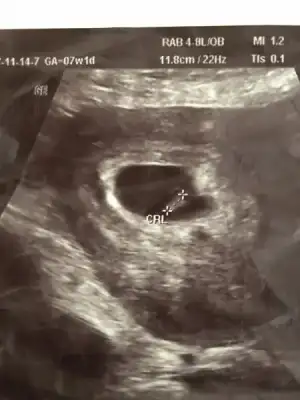

bebegin7-8 haftalıkkenki usg resimine direkt baktıgınızda;

bebek kesenin soluna yakınsa bebek erkek,

sagına yakınsa kız.